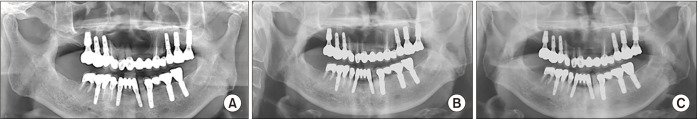

Results: A total of 147 teeth was included in this study. All the operated teeth underwent preoperative root canal treatment by an endodontic specialist. Apicoectomy was performed for 119 inflammatory cysts and 28 non-inflammatory cysts. Retrograde filling was performed on 22 teeth with inflammatory cysts and 3 teeth with non-inflammatory cysts. All teeth survived the 3.5-year follow-up (range, 1.0-9.1 years). However, 1 tooth with an inflammatory cyst developed complications 1 year after surgery that required re-endodontic treatment.

Conclusion: The prognosis of a tooth treated by apicoectomy without retrograde filling during cyst enucleation is favorable, regardless of the cyst type.